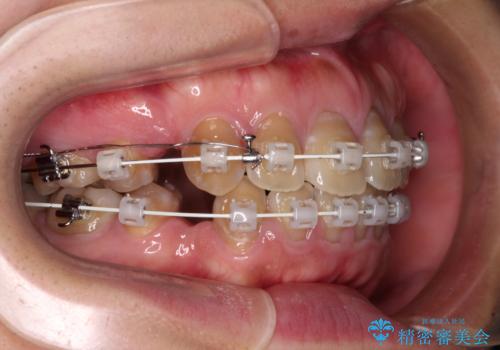

- 審美装置

- 2年6ヶ月

- 10-30回

上下前歯が著しく前突している状態であったので、上下左右の第1小臼歯4本を抜歯し、ワイヤー装置にて矯正治療を行うこととしました。